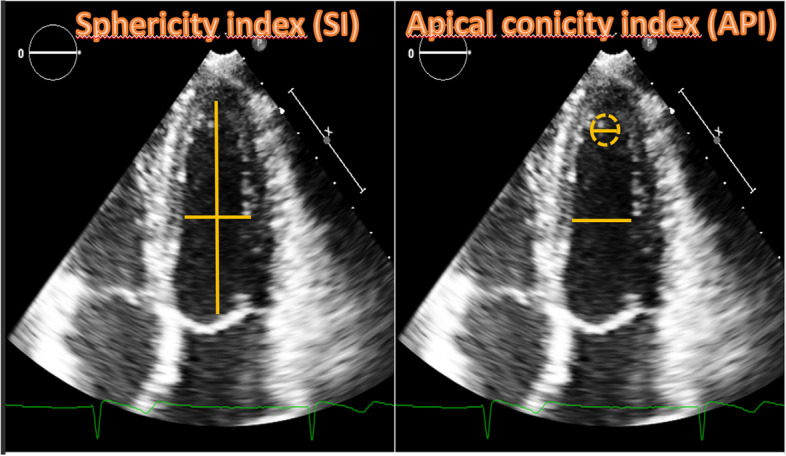

Methods: 21 female elite athletes (23.2 ± 5.3 years), 25 women with twin pregnancies (35.4 ± 5.7 years) and 25 healthy competitive female athletes (controls), age-matched with pregnant women (34.9 ± 7.9 years), were enrolled. This latter group was included to minimize the effect of age on cardiac remodeling. All women evaluated through anamnestic collection, physical examination, 12 leads ECG, standard echocardiogram and strain analysis. Sphericity (SI) and apical conicity (ACI) indexes were also calculated.

Results: Pregnant women showed higher LA dimension (p < 0.001) compared to both groups of athletes. LV e RV GLS were significantly different in pregnant women compared to female athletes (p = 0.02 and 0.03, respectively). RV GLS was also different between pregnant women and controls (p = 0.02). Pregnant women showed significantly higher S' wave compared to female athletes (p = 0.02) but not controls. Parameters of diastolic function were significantly higher in athletes (p = 0.08 for IVRT and p < 0.001 for E/A,). SI was lower in athletes in both diastole (p = 0.01) and systole (p < 0.001), while ACIs was lower in pregnant women (p = 0.04).